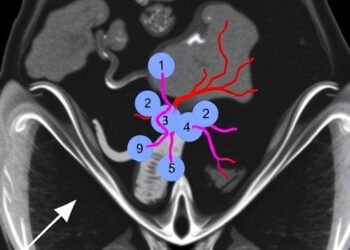

Unveiling Uterine Blood Vessels in Adenomyosis via 3D Imaging

In a groundbreaking study published in Angiogenesis, researchers have harnessed the power of 3D synchrotron X-ray imaging to illuminate the ...